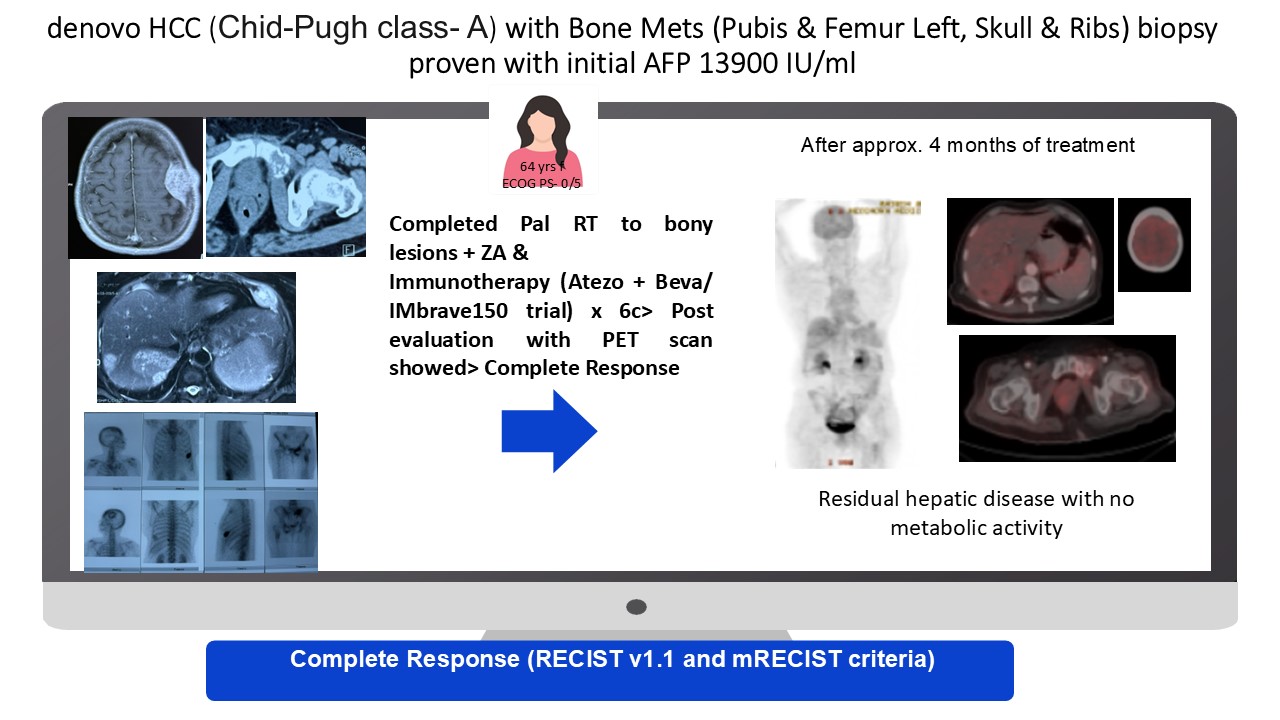

mHCC Survivor

NA